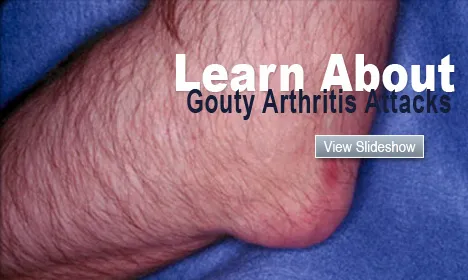

Watch & Learn About Gout

Watch this slideshow on gout (gouty arthritis) caused by crystals of uric acid deposits. Learn about treatment, causes, symptoms and medication for this painful condition.

Gout

Gout and hyperuricemia are caused by uric acid crystals building up in the body. Gout symptoms and signs include joint pain and swelling. Read about treatment and foods to avoid.

Gout Attack Symptoms, Causes, Treatment, and Diet

Gout Attack Symptoms, Causes, Treatment, and DietGout attacks (gouty arthritis) are caused by crystals of uric acid deposits. Learn about symptoms, causes, treatments and medication for this painful condition.